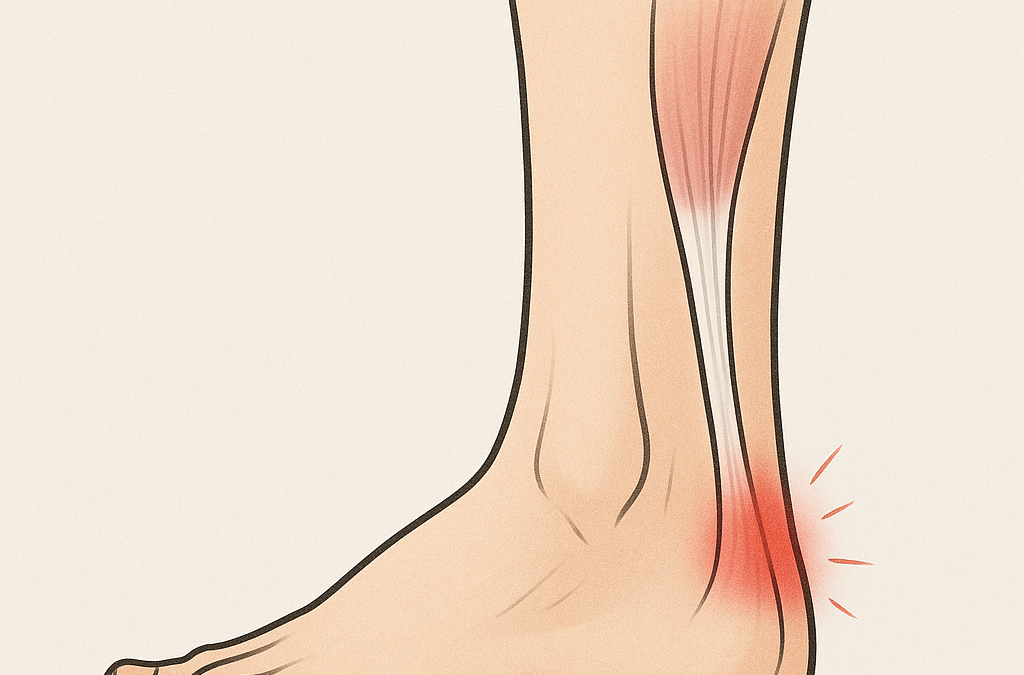

Sommaren är en tid då många kommer igång med löpning, promenader eller padel – och då märks det snabbt om något inte riktigt hänger med. En vanlig överbelastning som ofta dyker upp just nu är hälseneinflammation, eller achillestendinopati. Det börjar kanske som ett...